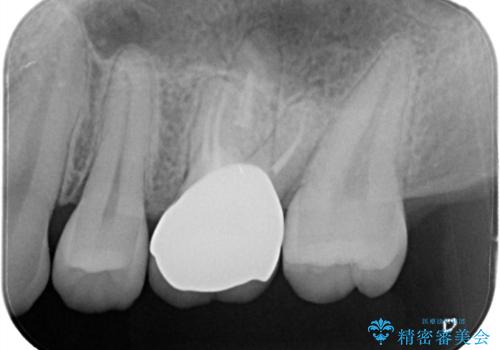

大きい虫歯 根管治療〜オールセラミッククラウン

- 歯が欠けたことを主訴に来院されました。

再根管治療後、歯周外科を行い、オールセラミッククラウンにて修復処置を行っております。

根管治療を行った大臼歯は速やかに被せ物の治療を行うことが必要です。